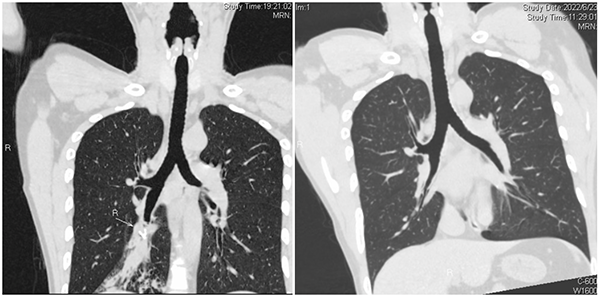

黃淮網(wǎng) 6月20晚,徐醫(yī)附院急診接診一位由邳州緊急轉(zhuǎn)診的特殊病人。當(dāng)日中午,患者進(jìn)食嗆咳后痰中帶血,至當(dāng)?shù)蒯t(yī)院查CT考慮右肺下葉氣管內(nèi)異物。呼吸與危重癥醫(yī)學(xué)科的張文輝主任接到急診會(huì)診電話后,迅速趕往急診現(xiàn)場,立即行氣管三維重建和增強(qiáng)掃描,發(fā)現(xiàn)右肺下葉類圓形的異物,直徑約6.6mm,異物位于亞段支氣管遠(yuǎn)端,不易取出,可能會(huì)導(dǎo)致大咯血,立即收入呼吸ICU進(jìn)一步治療。

呼吸ICU團(tuán)隊(duì)李元芹副主任醫(yī)師、嵇桂娟副主任醫(yī)師及呼吸內(nèi)鏡團(tuán)隊(duì)孫理想主治醫(yī)師仔細(xì)閱讀胸部CT表現(xiàn),發(fā)現(xiàn)該患者右肺下葉體積縮小,出現(xiàn)阻塞性炎癥,支氣管粘液嵌塞,說明異物并非短期吸入。追問患者,患者近五年反復(fù)咳嗽,誤當(dāng)支氣管肺炎治療。為盡快明確異物阻塞位置和管腔內(nèi)情況,在入院當(dāng)天行RICU床旁氣管鏡探查。在嵇桂娟副主任醫(yī)師、李海俠主管護(hù)師的配合下,孫理想醫(yī)師小心翼翼地將支氣管鏡輸送到病人氣道,逐個(gè)葉段仔細(xì)探查,發(fā)現(xiàn)右肺下葉基地段開口見一膜狀物堵塞,氣道幾乎完全閉鎖,同時(shí)吸出大量血性分泌物。

患者醒后回憶可能幾年前甚至孩童時(shí)期不慎誤吸該金屬物,他不忘給醫(yī)護(hù)人員點(diǎn)贊:“徐醫(yī)附院水平?jīng)]說的,太感謝了!”呼吸內(nèi)鏡治療后第二天復(fù)查CT,異物取出后右肺下葉氣管遠(yuǎn)端狹窄明顯改善。